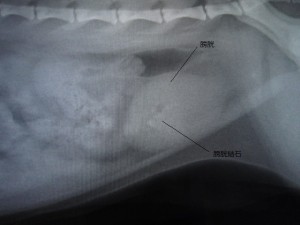

術前

術前のレントゲンです。

膀胱結石が見られます。